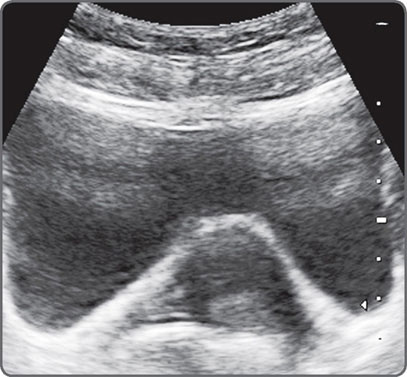

Power and Gain are not the same. Power level refers to the amount of energy produced by the transducer.4 Gain amplifies returning waves. Increasing the power helps to image deeper structures. It may, however, produce secondary vibrations in tissues. This can produce ring-down artefacts (Fig. 5). Some sound energy may bounce back and forth within a cyst resulting in reverberation artefacts (Fig. 6).

Fig. 6: Reverberation artefact. High-level echoes are seen in the anterior extent of the urinary bladder. These may obscure solid lesions and also render an entirely fluid lesion echogenic